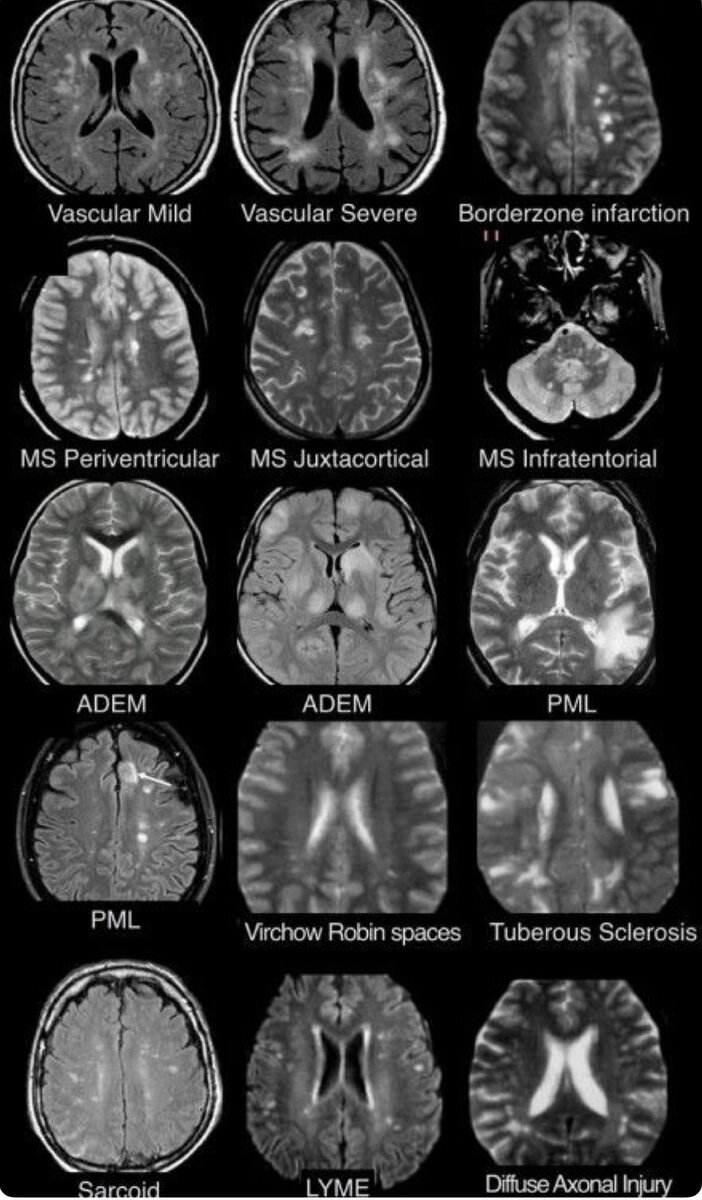

Очаги на МРТ могут означать не только Рассеянный Склероз

Существует много сходных заболеваний, без пункции можно ошибиться в диагнозе.